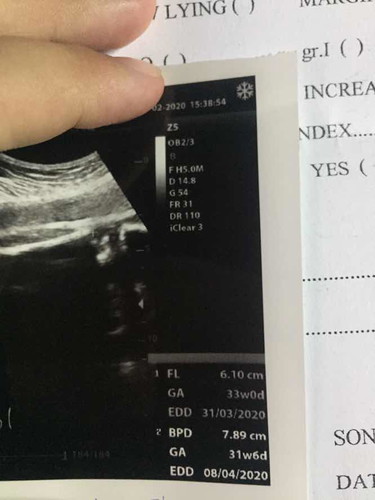

ตรงมุมล่างขวาคืออะไรหรอคะ ใช่สัปดาห์กับวันที่กำหนดคลอดไหมคะ แล้วทำไมมี 2 อัน รบกวนแม่ๆหน่อยนะคะ ขอบคุณค่ะ

FL = การวัดความยาวกระดูกต้นขา BPD = การวัดความกว้างของศีรษะทารก ส่วนอายุครรภ์ กับกำหนดคลอดในใบอัลตราซาวด์ มาจากการวัดส่วนต่างๆของน้องค่ะ ซึ่งจะไปค่อยตรงกับอายุครรภ์ กับกำหนดคลอดจากการนับ ปจด